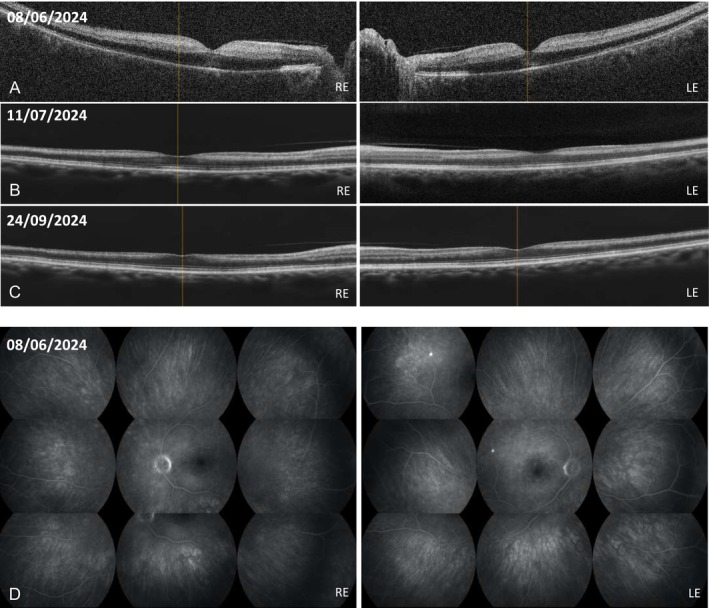

在这里,我们描述了一个罕见的嗜酸性肉芽肿病合并多血管炎(EGPA)在贝那利珠单抗治疗下表现为双侧视网膜中央动脉闭塞(CRAO)。患者为61岁男性,患有慢性嗜酸性鼻窦炎和严重哮喘,突然双侧视力丧失和短暂性黑朦。眼科检查,包括眼底检查和光学相干断层扫描,证实CRAO,实验室检查结果显示炎症标志物升高,在嗜酸性粒细胞计数正常的情况下,抗髓过氧化物酶抗体阳性。强化免疫抑制治疗导致全身性炎症消退,但仍存在明显的视力损害。这些发现强调了抗白细胞介素-5受体治疗在预防EGPA血管并发症方面的潜在局限性。

Here, we describe a rare presentation of eosinophilic granulomatosis with polyangiitis (EGPA) under benralizumab therapy manifesting as bilateral central retinal artery occlusion (CRAO). The patient, a 61-year-old man with chronic eosinophilic rhinosinusitis and severe asthma, experienced sudden bilateral visual loss and transient amaurosis. Ophthalmologic evaluations, including a fundus examination and optical coherence tomography, confirmed CRAO, and laboratory test results revealed elevated markers of inflammation and positive antimyeloperoxidase antibodies in the context of normal eosinophil counts. Intensive immunosuppressive therapy led to resolution of systemic inflammation, although significant visual impairment persisted. These findings underscore the potential limitations of anti-interleukin-5 receptor therapy in preventing vasculitic complications in EGPA.